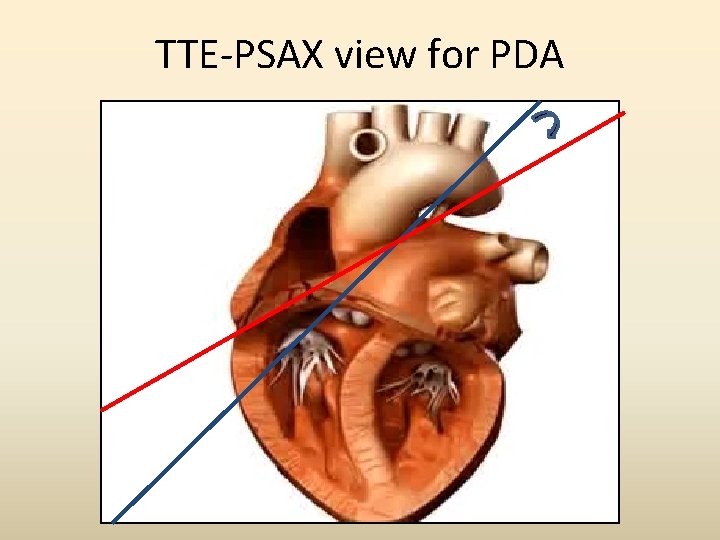

TTE- PSAX view The 1 st step in imaging the ductus is knowing where to look for it. Superior and leftward sweep of a routine Basal PSAX view

TTE-PSAX view for PDA